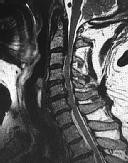

Figures 1 and 2 show sagittal and axial MRI from an 83-year-old woman with an ataxic gait, loss of dexterity, and intermittent loss of bowel and bladder control. The symptoms have been getting progressively worse over the past several weeks.

What disease process is most likely the cause of the patient’s symptoms?

4. Pigmented villonodular synovitis Discussion: B

The patient has a pannus at the C1-2 articulation that is compressing the spinal cord and causing myelopathy symptoms. The development of a pannus at this location has been associated with rheumatoid arthritis. Steinberger and associates showed increased morbidity and mortality when using an anterior approach and the surgery took longer than 4 hours. Chieng and associates showed better outcomes and lower complications rates using a posterior approach.

CLINICAL SITUATION

When discussing anterior versus posterior surgical techniques, you counsel this patient that

Discussion: A